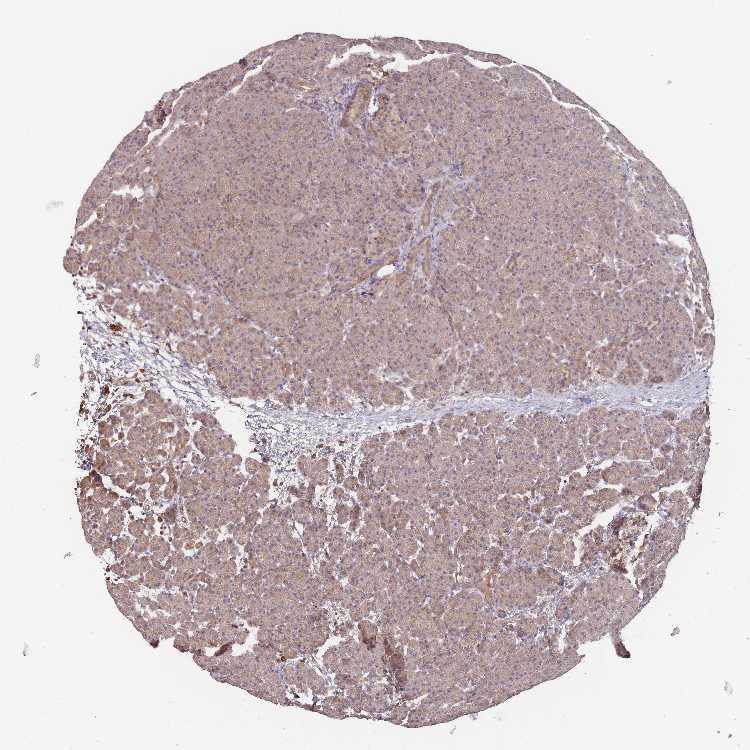

PANCREAS - Antibody stainingi

Antibody staining in the annotated cell types in the current human tissue is reported as not detected, low, medium, or high, based on conventional immunohistochemistry profiling in selected tissues. This score is based on the combination of the staining intensity and fraction of stained cells.

Each image is clickable and will lead to virtual microscopy that enables deeper exploration of all samples and also displays staining intensity scores, fraction scores and subcellular localization as well as patient and tissue information for each sample.

Antibody HPA043966

Exocrine glandular cells Low

Pancreatic endocrine cells Low